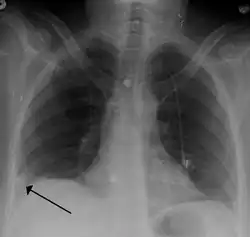

Low probability diagnostic tests/non-diagnostic tests

Tests that are frequently done that are not sensitive for PE, but can be diagnostic.

- Chest X-rays are often done on people with shortness of breath to help rule out other causes, such as congestive heart failure and rib fracture. Chest X-rays in PE are rarely normal,[70] but usually lack signs that suggest the diagnosis of PE (for example, Westermark sign, Hampton's hump).